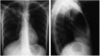

- 2-5mm radio-opaque nodules on CXR

- Nodular opacities occur primarily in the upper lung fields in simple version

- May become more widespread and then confluent with progression to large opacities in complicated version with progressive massive fibrosis

Pneumoconiosis – Coal Worker’s Lung

simple coal workers pneumoconiosis

complicated coal workers pneumoconiosis

•2-5mm radio-opaque nodules on CXR

Dust particles in the alveoli are ingested by macrophages which then become “coal macules”